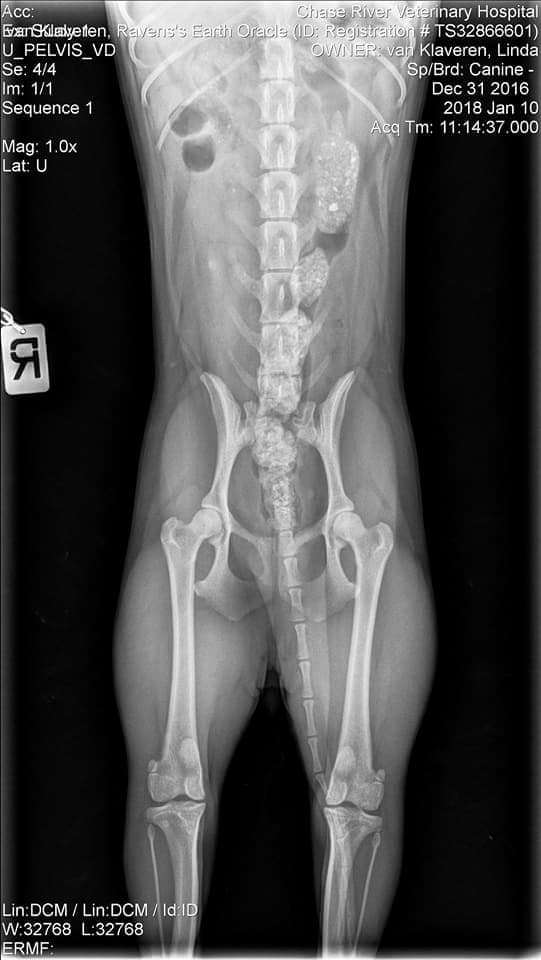

OFA Test Results:

Test Date - Jan. 10, 2018

Report Date - Jan. 15, 2018

· HIPS PRELIMINARY GOOD

· CHC-LP23/12F-VPI LEGG-CALVE-PERTHES NORMAL

· CHC-PA676/12F/P-VPI PATELLA NORMAL - PRACTITIONER